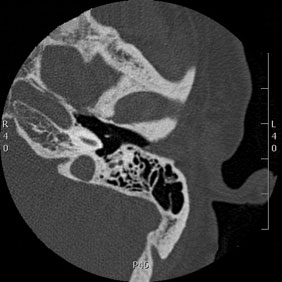

Tomografía computarizada Oídos

< Volver a "Tomografía Computarizada (TC) con Inteligencia artificial"Se utiliza para el estudio de las estructuras del oído interno, los peñascos o las celdas mastoideas.